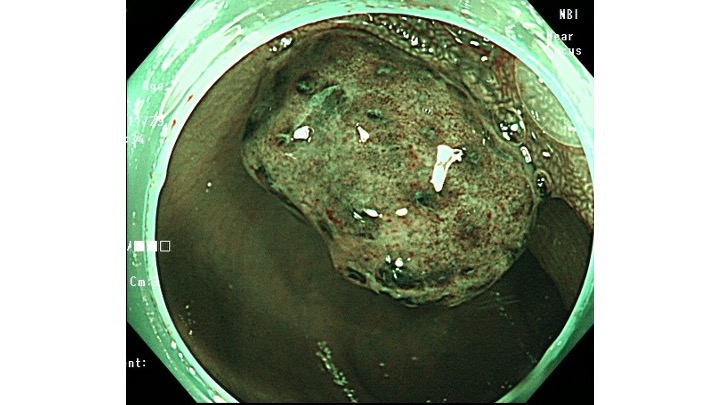

NBI観察では、大小不同の類円形のPitがあることから、若年性ポリープの診断で、その場で内視鏡的切除をしています。